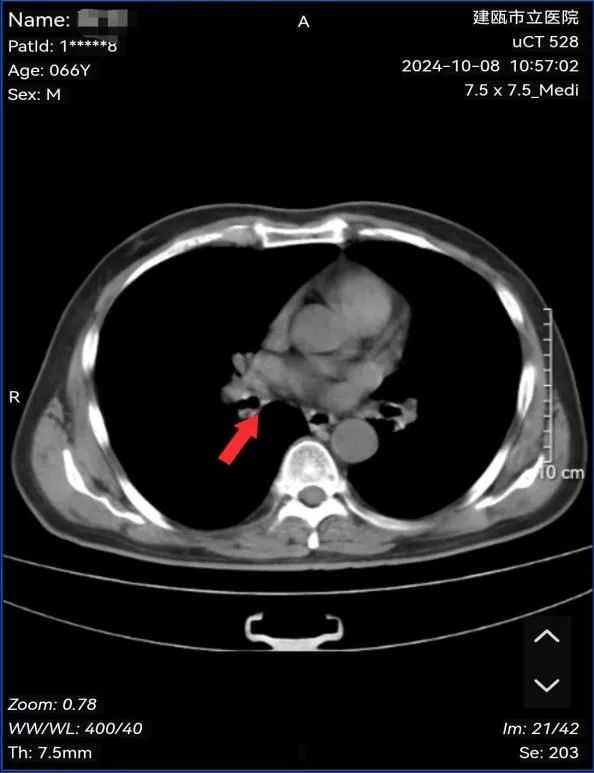

面对高度侵袭性的小细胞肺癌,我院肺癌MDT小组第一时间组织专家与省肿瘤医院专家对患者病情开展MDT讨论、联合查房,制定了详细的诊疗计划,先期在我院行2周期静脉化疗,此后转至福建省肿瘤医院行同步放化疗治疗,经过3个月治疗后,近期患者在我院复查疗效达到完全缓解(cCR),针对是否进行后续全脑预防性放疗及免疫维持在本次线上线下联合查房中进行了探讨。目前局限期小细胞肺癌同步放疗后进行免疫维持治疗取得重大进展,多学科探讨个性化治疗对于延长生存至关重要。

图为:治疗后病灶影像结果(原右肺下叶病灶消失)